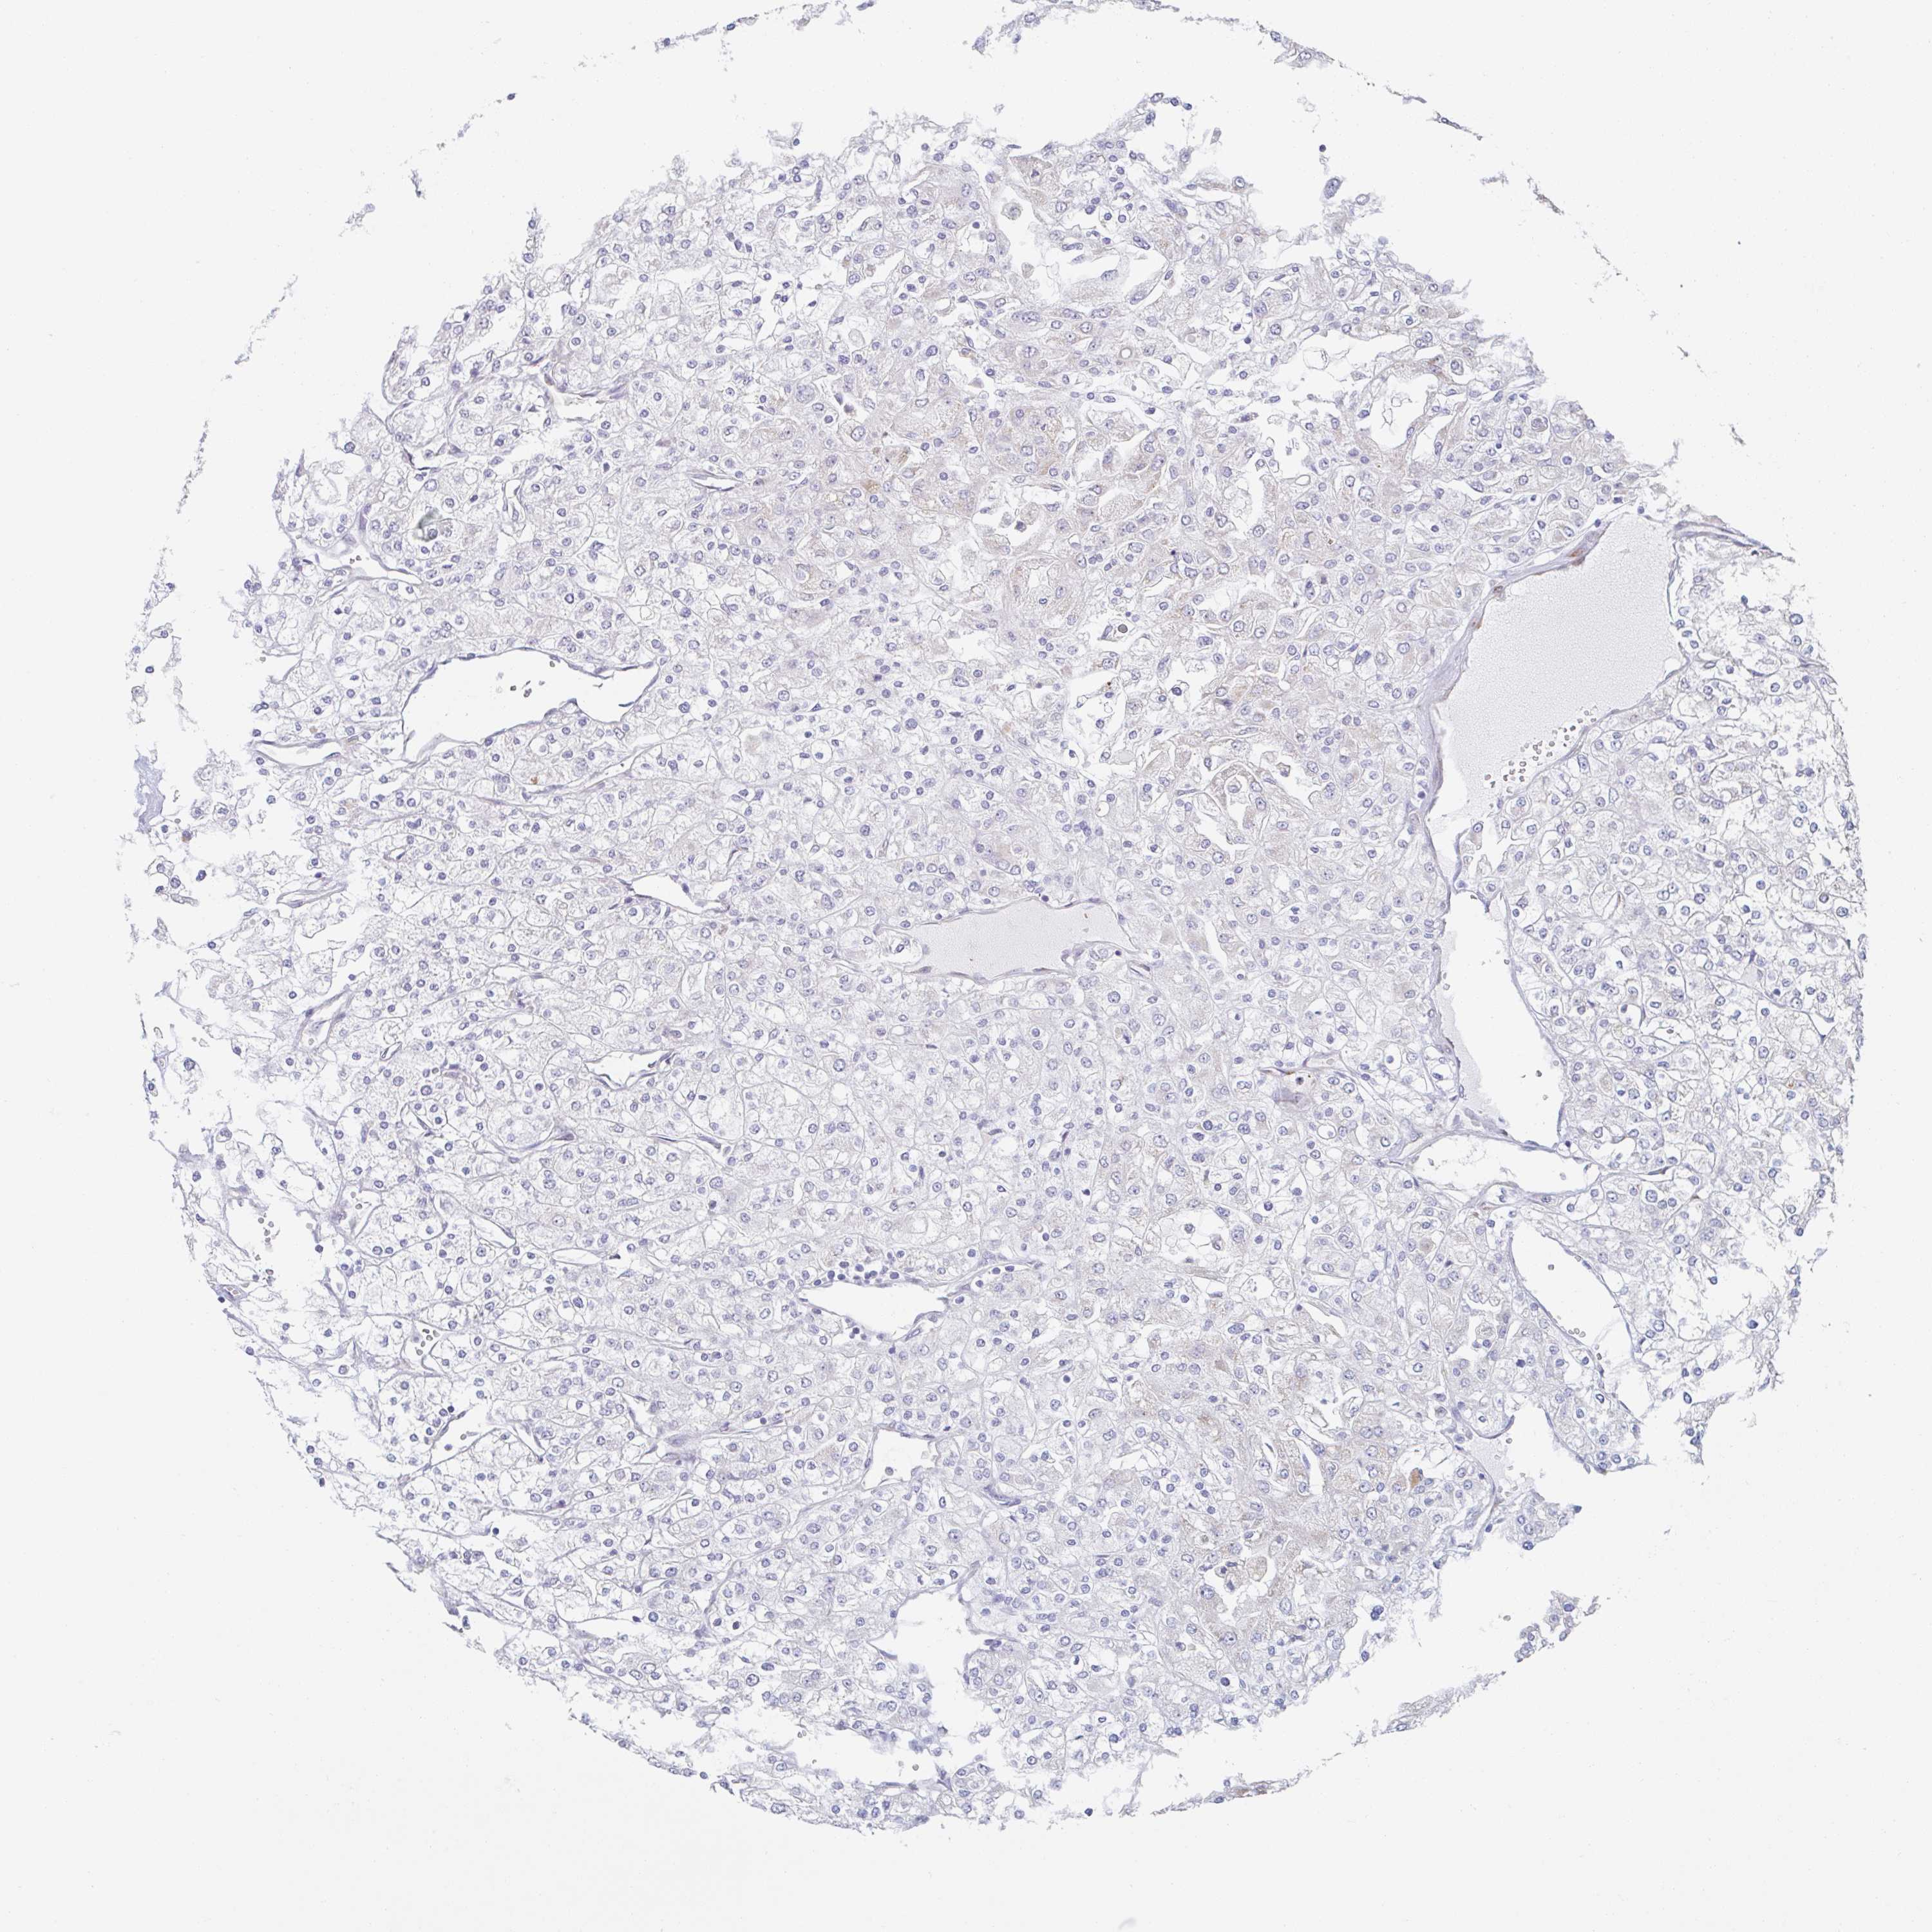

CANCER RENAL CANCER Show tissue menu

KICH TCGA KIRC TCGA KIRC VALIDATION KIRP TCGA PROTEIN RCC CPTAC PROTEIN EXPRESSION